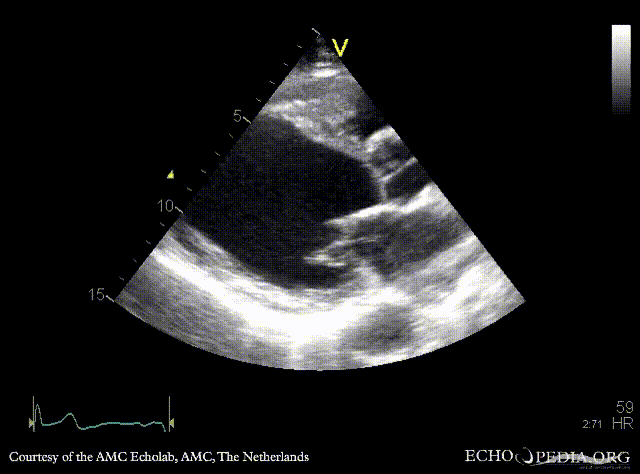

Apical aneurysm of LV

A4CH: dilated left ventricle, apical aneurysm A2CH: apical aneurysm